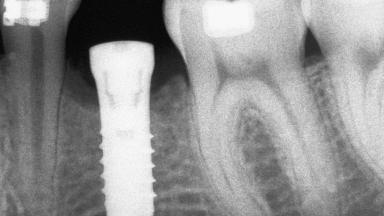

An 18-year-old man was referred for implant therapy in the posterior mandible to the Department of Oral Surgery and Stomatology (University of Bern, Switzerland). He was healthy and did not smoke. Tooth 35 was congenitally missing, involving a single-tooth edentulous space that offered an adequate mesiodistal dimension for implant placement but exhibited a typical pattern of buccal flattening. A panoramic radiograph was obtained, which revealed a sufficient vertical bone height above the mandibular canal and a normal bone structure in the edentulous area.